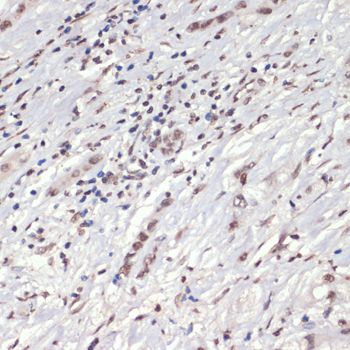

Immunohistochemistry of paraffin-embedded human liver cancer using Phospho-Jak2-Y1007/1008 antibody.

Immunohistochemistry of paraffin-embedded human lung cancer using Phospho-Jak2-Y1007/1008 antibody. |